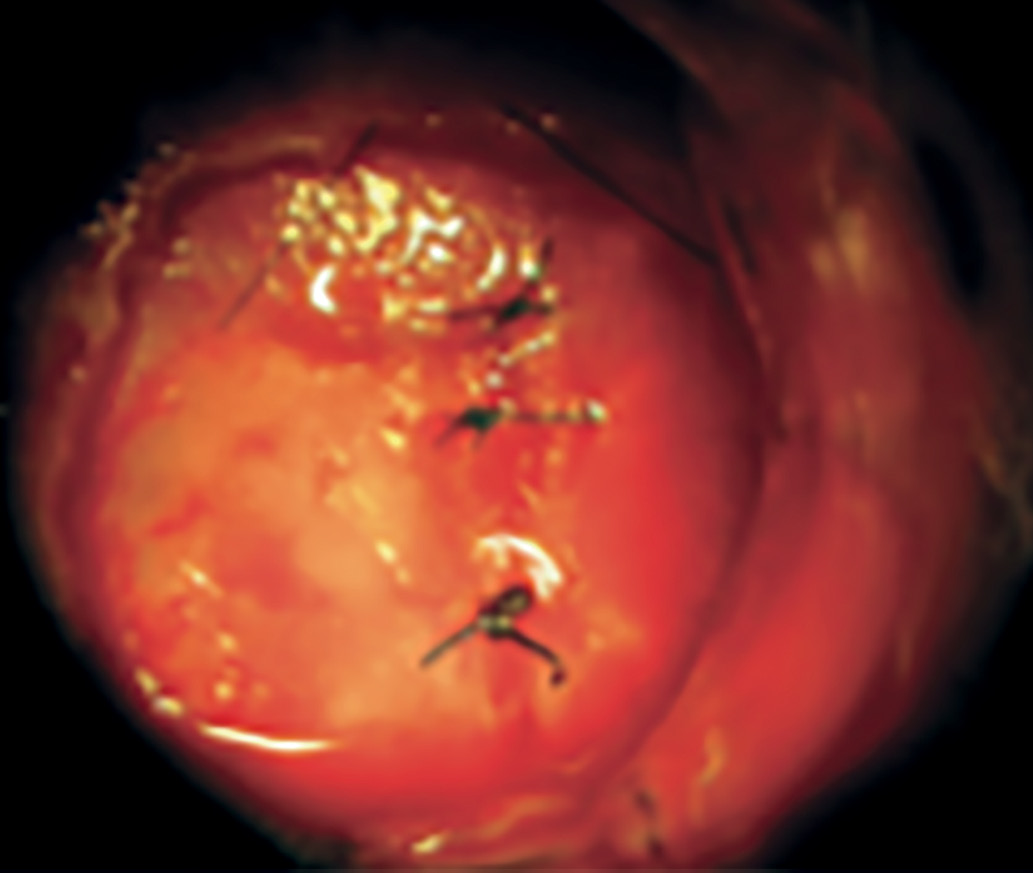

Хирургическое лечение опухолей гипофиза включает три основных стадии, или этапа: назальный, сфеноидальный и селлярный. На каждой стадии хирургу необходимо пройти через те или иные структуры, применяя различные инструменты и оборудование. Если костные структуры выраженные и плотные, то хирургу приходится использовать высокоскоростной бор, которым можно высверлить отверстие нужного диаметра как в области входа в основную пазуху, так и в передней стенке турецкого седла для последующего осуществления хирургического удаления опухоли (рис. 3).

Рисунок 3. Фрагмент операции во время осуществления доступа через костные структуры основной пазухи.